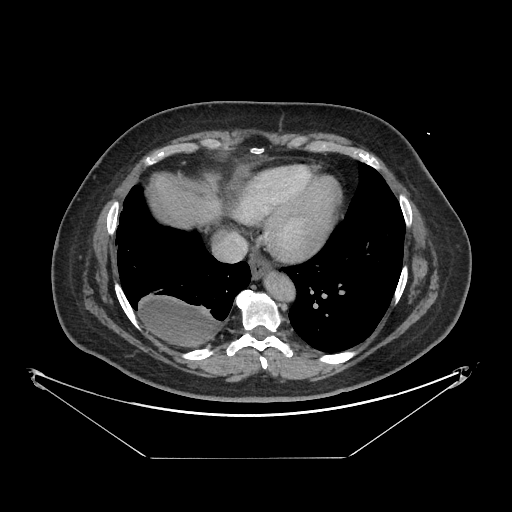

Image Grid

4Γ—3 grid: Rows show different image types (Original NATIVE, Reconstructed NATIVE, Original VENOUS, Generated VENOUS), Columns show windowing techniques (No Window, Lung Window, Mediastinum Window)

Original VENOUS CT scan

Full window (WL 1023.5, WW 4095 β†’ Low βˆ’1024, High +3071)